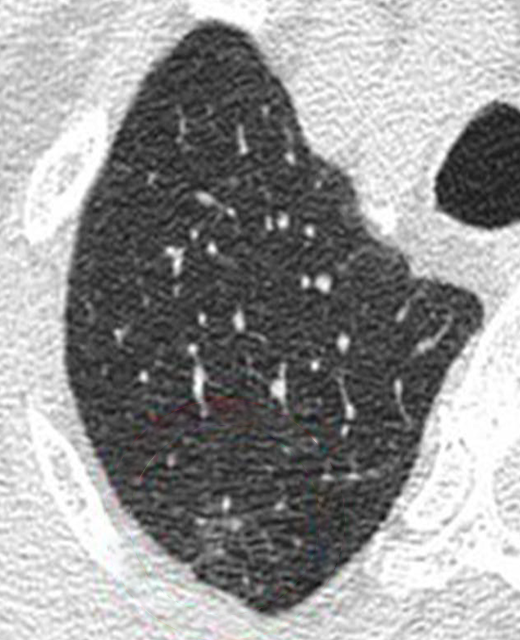

Ultra Low-Dose Scan

A regular scan at ultra-low dose radiation is noisy and unclear, making it possible to overlook a problem.

AIML

High-Dose Scan

The same scan with a higher dose of radiation reveals an abnormality.

AI Enhanced Ultra Low-Dose Scan

Our AI technology is able to sharpen the quality of the ultra-low dose scan to assist the doctor in early detection.